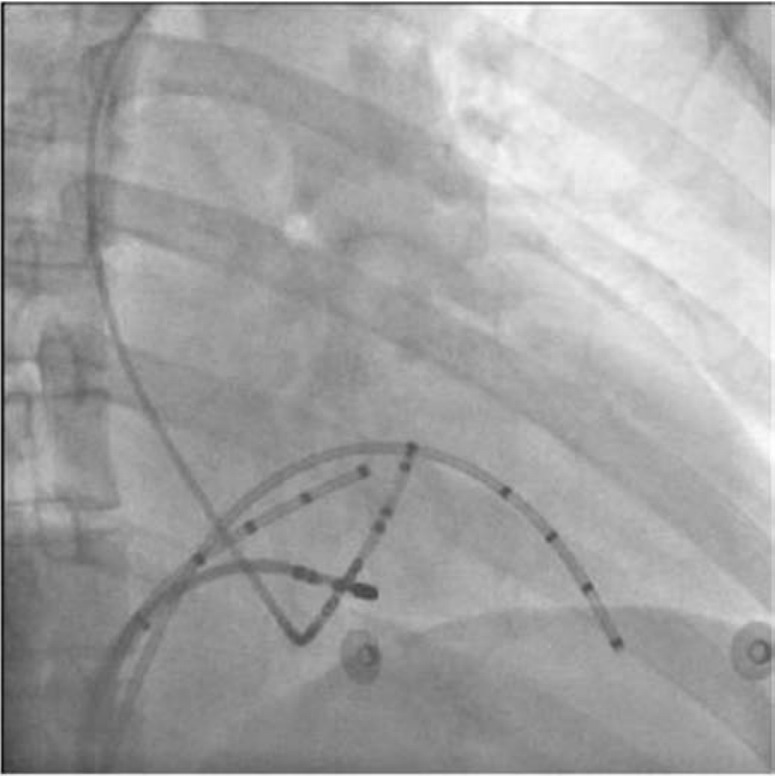

X线靶点见下图

img1697

RAO30°

img1698

LAO45°